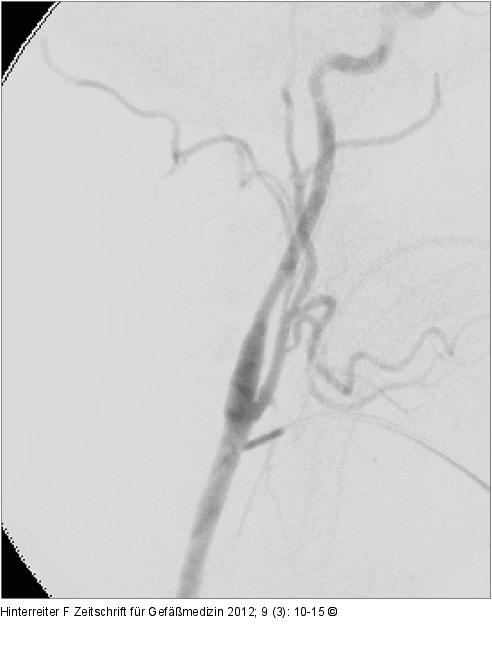

Abbildung 5: Angiographie

Intraoperative Angiographie